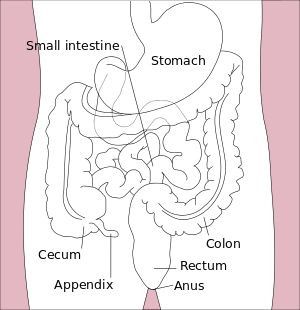

| Diagram of the lower gastrointestinal tract | |

Colorectal cancer (CRC), also known as bowel cancer, is the development of cancer from the colon or rectum (parts of the large intestine).[1] It is due to the abnormal growth of cells that have the ability to invade or spread to other parts of the body.[2] Signs and symptoms may include blood in the stool, a change in bowel movements, weight loss, and feeling tired all the time.[3]